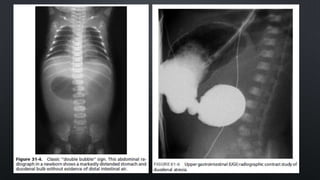

• THE DIAGNOSTIC RADIOGRAPHIC PRESENTATION (UPRIGHT ABDOMINAL RADIOGRAPH) 

“DOUBLE BUBBLE” SIGN WITH NO DISTAL BOWEL GAS

• THE PROXIMAL LEFT-SIDED BUBBLE  AIR- AND FLUID-FILLED STOMACH

• THE SECOND BUBBLE TO THE RIGHT  THE DILATED PROXIMAL DUODENUM

• HOWEVER, THE PRESENCE OF DISTAL GAS DOES NOT EXCLUDE THE DIAGNOSIS OF ATRESIA

• LIMITED UPPER GASTROINTESTINAL CONTRAST STUDY  TO EXCLUDE MALROTATION AND

VOLVULUS

CONT’D • ABDOMINAL DISTENTIONMAY OR MAY NOT BE PRESENT, DUODENAL ATRESIA  SCAPHOID • ASPIRATION VIA A NASOGASTRIC TUBE > 20 ML (N: < 5 ML) • THE DIAGNOSTIC RADIOGRAPHIC PRESENTATION (UPRIGHT ABDOMINAL RADIOGRAPH)  “DOUBLE BUBBLE” SIGN WITH NO DISTAL BOWEL GAS • THE PROXIMAL LEFT-SIDED BUBBLE  AIR- AND FLUID-FILLED STOMACH • THE SECOND BUBBLE TO THE RIGHT  THE DILATED PROXIMAL DUODENUM • HOWEVER, THE PRESENCE OF DISTAL GAS DOES NOT EXCLUDE THE DIAGNOSIS OF ATRESIA • LIMITED UPPER GASTROINTESTINAL CONTRAST STUDY  TO EXCLUDE MALROTATION AND VOLVULUS